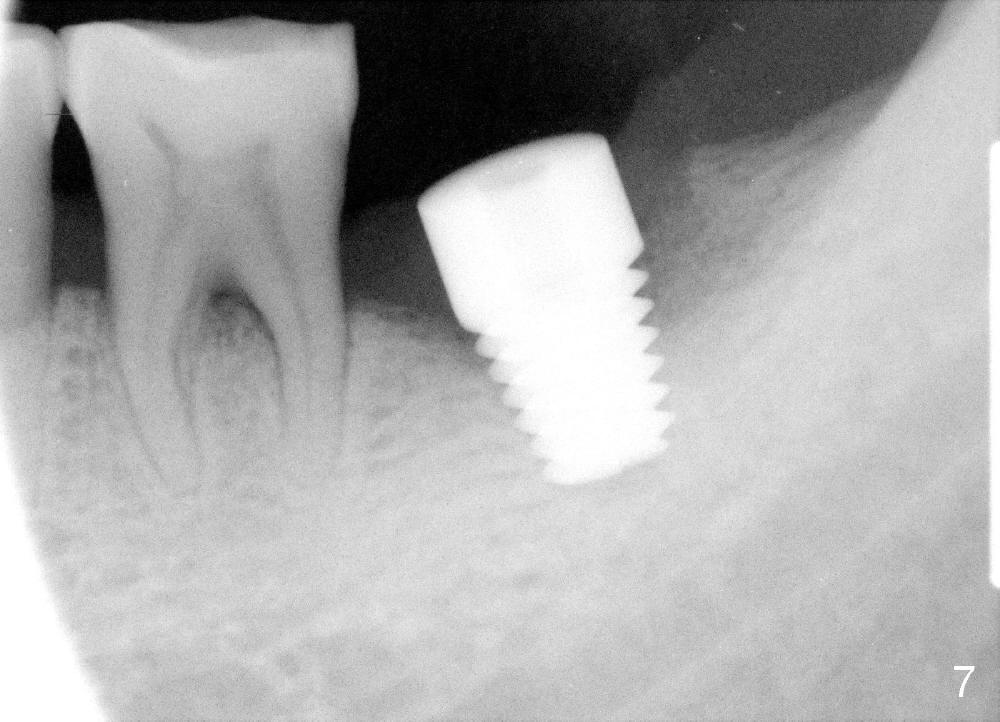

A 51-year-old man has generalized chronic periodontitis. The mesial root of #18 has vertical fracture (Fig.1*) with infection. The patient agrees extraction (Fig.2) and immediate implant. The septum is thin. The pilot drill drops into either the mesial (Fig.3) or distal sockets. Furthermore it is difficult to control pain probably due to severe infection (Fig.2 >: mesiobuccal erythema and edema). Repeated local infiltration does not alleviate pain associated with drilling. Block anesthesia has to be administered (one carpule of 2% Lidocaine with 1:100,000 Epinephrine). Damage to the inferior alveolar nerve (Fig.1 red dashed line) increases. On the other hand, osteotomy through the socket of the tooth with periodontits is easier because of shallow socket. Retraction of the buccal gingiva can reveal the bottom of the socket. We will increase the depth slowly until a tap obtains initial stability. The worst scenario is that active hemorrhage from the socket bottom is encountered initially. The nerve injury can be reduced minimally.

Now where to initiate osteotomy? Since the mesial crest is much lower than the distal (compare arrowheads in Fig.1), placement of an implant in the mesial socket is a good approach, whereas placement in the distal socket is not good for restoration (cantilever). The thin septum is slippery to drill penetration. What should we do?